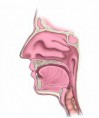

La deglución es el proceso por el cual, el alimento se mezcla con la saliva (bolo alimenticio) y consta de una fase bucal, una fase faríngea, y una fase esofágica.